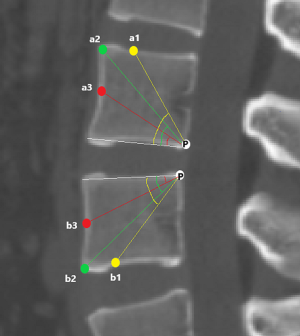

The angles of oblique fixation from posterior corner in lumbar spine in sagittal and axial planes (Figures 5-9).

a1: the angle between the line, which is from the posterior-lower corner of the upper vertebral body to front-middle 1/3 of the upper endplate, and lower endplate parallel line.

a2: the angle between the line, which is from the posterior-lower corner of the upper vertebral body to anterior-upper corner, and lower endplate parallel line.

a3: the angle between the line, which is from the posterior-lower corner of the upper vertebral body to the midpoint of the anterior border, and lower endplate parallel line.

b1: the angle between the line, which is from the posterior-upper corner of the lower vertebral body to front-middle 1/3 of the lower endplate, and upper endplate parallel line.

b2: the angle between the line, which is from the posterior-upper corner of the lower vertebral body to anterior-lower corner, and upper endplate parallel line.

b3: the angle between the line, which is from the posterior-upper corner of the lower vertebral body to the midpoint of the anterior border, and upper endplate parallel line.

The included angles a1, a2, a3, b1, b2, b3 and c1, c2 and c3 in the sagittal plane were significantly different (P≤0.001) (Figure 13) (a1 > a2 > a3, b1 > b2 > b3, c1 < c2 < c3). In the angles of sagittal down-path, b1, b2 and b3 change significantly and consistently, showing a trend of decreasing first and then increasing, which is the smallest at L3 (46.08±4.37°, 36.21±3.51°, 22.47±3.01°) and the largest at S1 (69.49±8.28°, 61.23±7.74°, 36.60±5.00°). In the angles of sagittal up-path, a1 and a2 change in the same way, showing an increasing trend. While a3 goes down and then goes up, which is the smallest at L4 (23.43±4.29°) and the largest at L5 (24.36±2.94°). In the angles of axial plane, c1, c2 and c3 change in the same way, showing a trend of increasing first and then decreasing. c1 and c2 are the largest at L2 (40.07±2.75°, 55.1±3.32°), and c3 is the largest at L3 (73.11±2.10°). c1, c2 and c3 are the smallest at S1 (33.87±2.94°, 47.92±3.54°, 67.15±3.60°) (Figures 14,15).

PETOFPC technique innovatively sets screws from posterior corner in lumbar spine in a regular 7.5-mm diameter channel. PETOFPC is also performed in the posterolateral transforaminal approach (Figure 18). A cylindrical sheath with an outer diameter of 7.5 mm were inserted in sequence. Through the sheath alone or the endoscope, the intervertebral disk and cartilaginous endplate were removed while confirming through percutaneous endoscopic observation that no cartilage remained. At the completion of the endplate preparation, the new integrated fixable and fused interbody cage was inserted into the intervertebral space (16). Before the new integrated fixable and fused interbody cages were expanded, we should clearly expose the screw entry point in posterior corner. The screw entry point is the bony area between the pedicle and the endplate. When intervertebral height was restored, the two wings of new integrated fixable and fused interbody cage splay to the sides and fit to posterior corner in lumbar spine (Figure 19). In the single 7.5-mm channel, endoscopic visualization was used to monitor placing screws to make the new integrated fixable and fused interbody cage fixed in lumbar spine. The angles of screw placement were made up of inward inclined angle, head tilt angle and tail tilt angle, namely c1, c2, c3, a1, a2, a3, b1, b2 and b3, all which was measured and analyzed in this study.